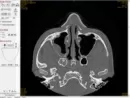

1,5 года назад получил в лицо удар кулаком. Через полгода после получения травмы сделали мне септопластику, но результата мне это не дало, всё равно принимал сосудосуживающие капли. После этого обратился за ринопластикой. Через год примерно после септопластики, врач поставил мне диагноз вдавленный перелом передней стенки, т.е. провалена кость вместе с частью орбиты глаза, что и затрудняет дыхание. Договорились сделать операцию по поднятию кости передней стенки, чтобы увеличить проход для дыхания. 22.07.18 г. меня прооперировали. 24.07.18 г. сняли турунды. Сегодня 25.08.18 жалобы такие: ноздря вдавленной стороны так и не дышит и не могу высморкаться этой стороной, воздух вдыхается очень трудно и выдыхать вообще не могу, ощущается постоянное давление внутри ноздри травмированной стороны, другая сторона ноздри дышит очень хорошо. 27.08.2018 сделал КТ, чтобы убедиться освободили мне проход для дыхания или нет. Прошел месяц со дня операции нос так и не дышит.

Прошло 1,5 года с момента травмы, по снимку отчетливо заметно сужение полости, но неизвестно каковы были изменения размеров полости до и после операции. Возможно, чувствительность восстановится через 3-4 месяца, Вы должны находиться под постоянным контролем ЛОР врача.